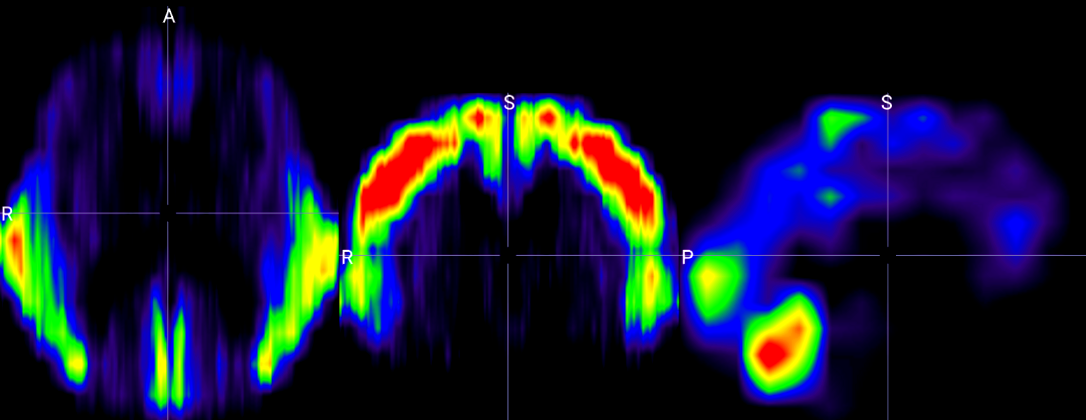

To further interpret the spatial focus of the Vision Transformer within the proposed BrainRotViT framework, we visualize the mean attention distribution across subjects in the validation set. Figure 4(a) illustrates the aggregated attention heatmap derived from the middle sagittal slice (slice index 80) averaged over all n=1022n=1022 validation samples. The 3D attention visualization in Figure 4(b) reveals several neuroanatomical regions exhibiting strong activation from the model, corresponding to areas known to undergo age-related structural and functional changes.

Figure 4: Model Interpretation. (a): Example of per-slice attention map extracted from vision transformer. (b) Mid-slice section views of fused 3D attention map along axial, coronal, and sagittal planes (from left to right).(c): Saliency map of trained residual CNN extracted through guided back propagation. (d)–(k): 3D attention map previews by age range.

The lower and medial posterior regions of the cerebellum show high attention concentration, reflecting their involvement in age-associated decline in motor coordination and memory consolidation, as has been supported by several studies [59, 60, 61]. Particularly the cerebellar vermis, whose volume has been strongly associated with aging-related changes [62, 63, 64], appears as a region that our aging model finds interesting invariably across age ranges. Close to the cerebellum, the cuneus is another region exhibiting high intensity in our attention maps. While recent studies using functional MRI data have noted changes in cuneus activation with age [65, 66], our study uses structural data only, thus hinting that with aging the cuneal cortex undergoes structural changes as well.

The precentral cortex, which exhibited high attention concentration in our model, has been linked with age-associated changes quite commonly in the literature. Prior studies have identified thinning of the precentral cortex and the atrophy of the primary motor cortex as quantitative markers of aging [67, 68]. One study compares such changes with the structural changes in the postcentral gyrus [69], which also appears as a high-attention region in our model. Functional differences in the primary motor cortex, which is located within the precentral cortex, have also been attributed to aging [70, 71, 72], thereby further substantiating the biological interpretability of our aging model.

Across all age ranges, the temporal lobes, particularly the middle temporal gyrus, remained as a prominent region of interest for our aging model. This coincides with several prior studies that have confirmed the role of the temporal lobes in aging and neurodegeneration [73, 74, 75]. Moreover, comparing the volume of the region of relative intensity greater than 0.4 near the temporal gyrus between all age groups (Figures 4(d)4(k)), it was observed that the volume of the high-attention region in the temporal lobe increases with age, suggesting that changes in the temporal lobes accelerate with age, which is also supported by Fujita et al. (2023) [76].

While slightly higher than average attention concentration was observed in a part of the frontal lobe, in general the frontal lobe exhibited relatively lower attention weight compared to postcentral and cerebellar regions (Figure 4(b)). However, it was observed that the intensity of attention applied by the model to the frontal lobe varies significantly by age group (Figures 4(d)4(k)). Sampling the intensity in a region in the medial part of the superior frontal gyrus, the greatest intensity was found among samples in the 10-20 year age group. This suggests that the frontal lobe undergoes the most rapid change specifically in adolescence and early adulthood, as is backed by numerous prior studies [77, 78, 79, 80].